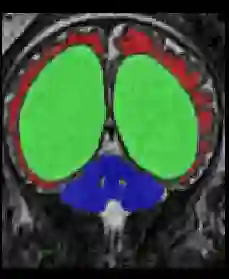

Limiting failures of machine learning systems is of paramount importance for safety-critical applications. In order to improve the robustness of machine learning systems, Distributionally Robust Optimization (DRO) has been proposed as a generalization of Empirical Risk Minimization (ERM). However, its use in deep learning has been severely restricted due to the relative inefficiency of the optimizers available for DRO in comparison to the wide-spread variants of Stochastic Gradient Descent (SGD) optimizers for ERM. We propose SGD with hardness weighted sampling, a principled and efficient optimization method for DRO in machine learning that is particularly suited in the context of deep learning. Similar to a hard example mining strategy in practice, the proposed algorithm is straightforward to implement and computationally as efficient as SGD-based optimizers used for deep learning, requiring minimal overhead computation. In contrast to typical ad hoc hard mining approaches, we prove the convergence of our DRO algorithm for over-parameterized deep learning networks with ReLU activation and a finite number of layers and parameters. Our experiments on fetal brain 3D MRI segmentation and brain tumor segmentation in MRI demonstrate the feasibility and the usefulness of our approach. Using our hardness weighted sampling for training a state-of-the-art deep learning pipeline leads to improved robustness to anatomical variabilities in automatic fetal brain 3D MRI segmentation using deep learning and to improved robustness to the image protocol variations in brain tumor segmentation. Our code is available at https://github.com/LucasFidon/HardnessWeightedSampler.